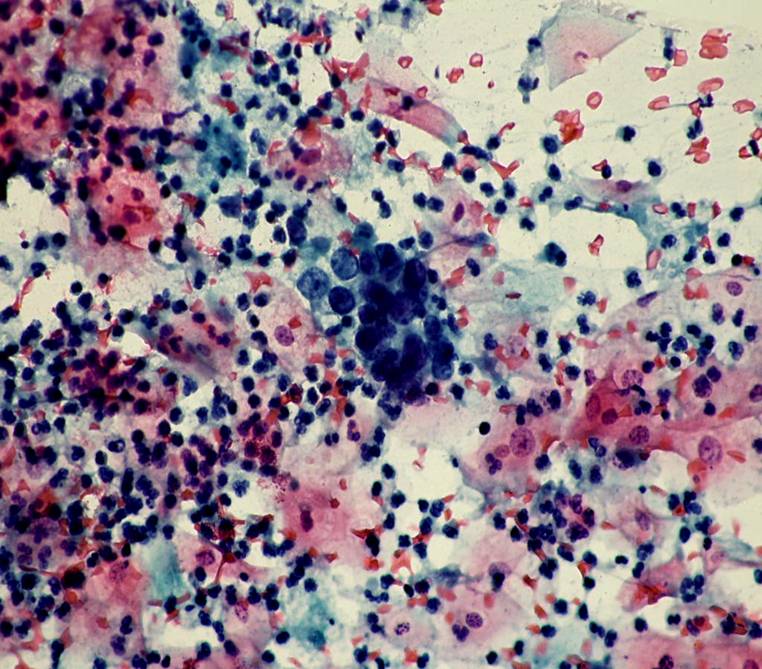

TBS-85.子宫内膜腺癌

TBS-86.子宫内膜腺癌

TBS-87.子宫内膜腺癌

TBS-88.子宫内膜腺癌

TBS-89.子宫内膜腺癌